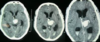

**IVH** - On CT imaging it appears as hyperdensity within the dark CSF spaces within the ventricles.

Subdural on CT head

**Intraventricular haemorrhage**: hyperintense (bright) blood within the ventricles (with a fluid level); may be **primary**: started in ventricles or **secondary**: extension of extra-ventricular bleed (usually SAH or intracerebral e.g. basal ganglia)